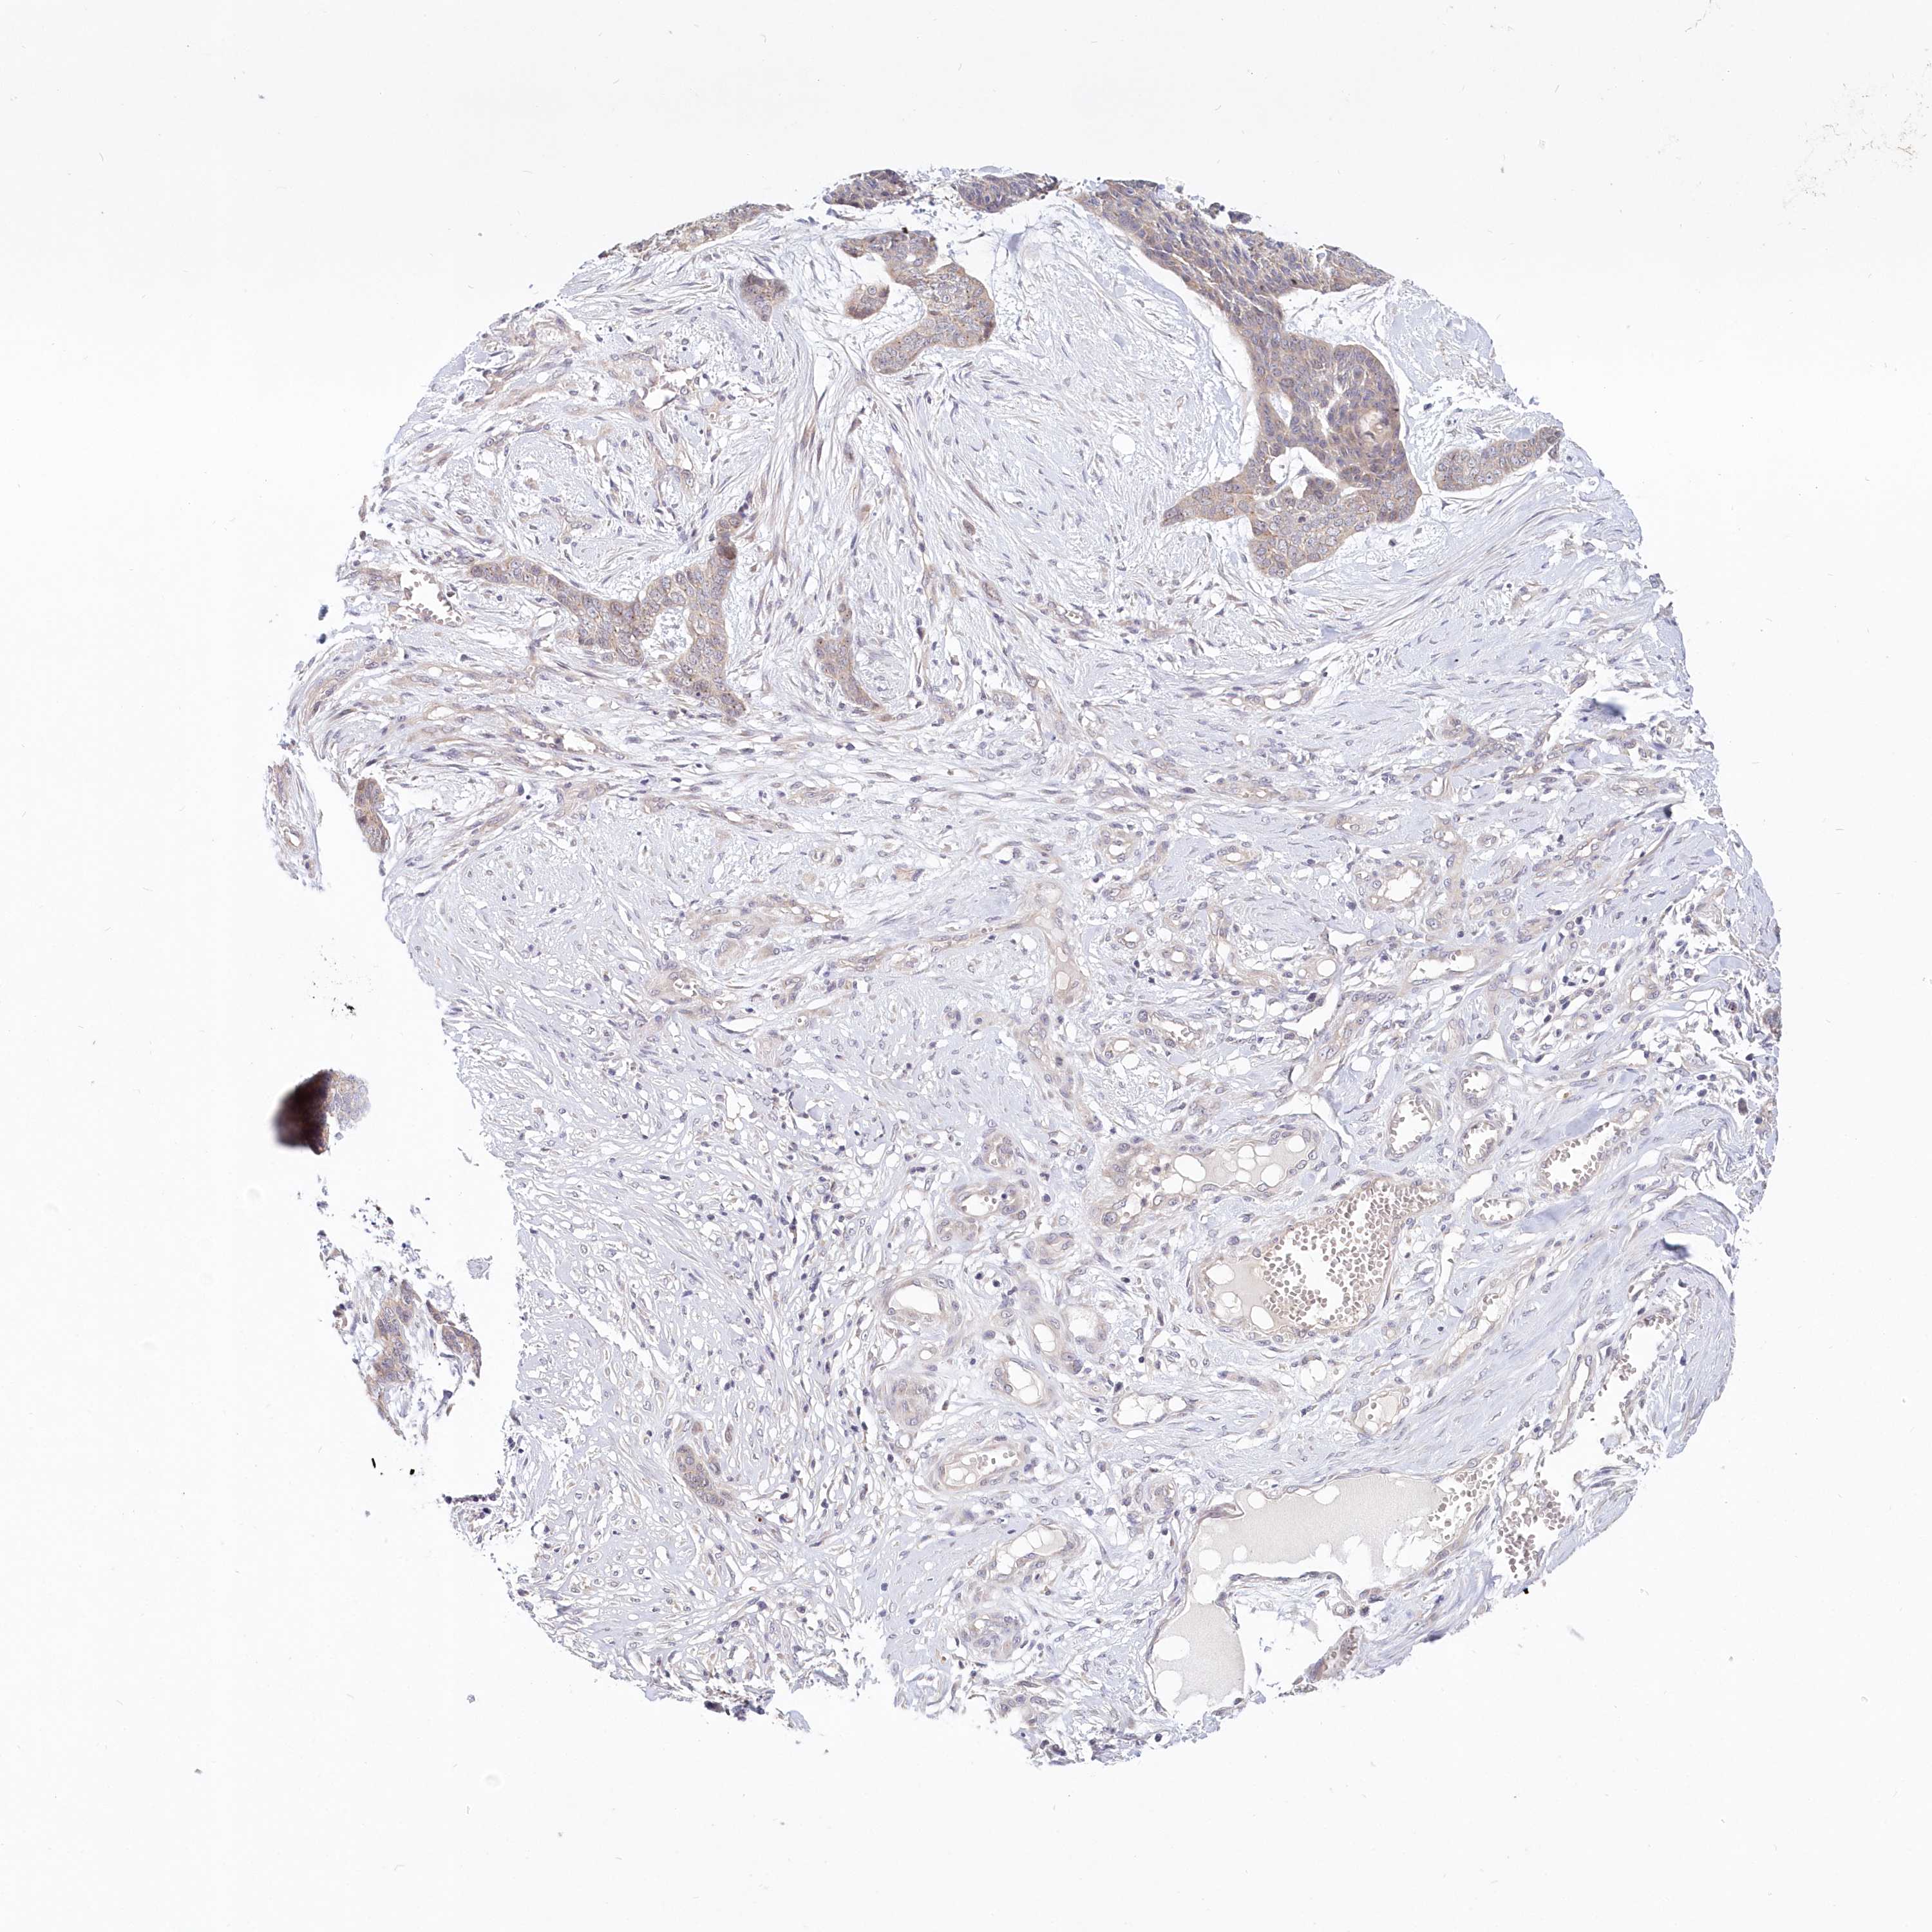

Basal cell and squamous cell cancer

SKIN CANCER - Protein expressioni

A mouse-over function shows sample information and annotation data. Click on an image to view it in a full screen mode. Samples can be filtered based on level of antibody staining by selecting one or several of the following categories: high, medium, low and not detected. The assay and annotation is described here.

Antibody stainingi

Antibody staining in the annotated cell types in the current human tissue is reported as not detected, low, medium, or high, based on conventional immunohistochemistry profiling in selected tissues. This score is based on the combination of the staining intensity and fraction of stained cells.

Each image is clickable and will lead to virtual microscopy that enables deeper exploration of all samples and also displays staining intensity scores, fraction scores and subcellular localization as well as patient and tissue information for each sample.

Antibody HPA036207

Staining

High

Medium

Low

Not detected

Intensity

Strong

Moderate

Weak

Negative

Quantity

>75%

75%-25%

<25%

None

Location

Nuclear

Cytoplasmic/membranous

Cytoplasmic/membranous,nuclear

Squamous cell carcinoma, metastatic, NOS